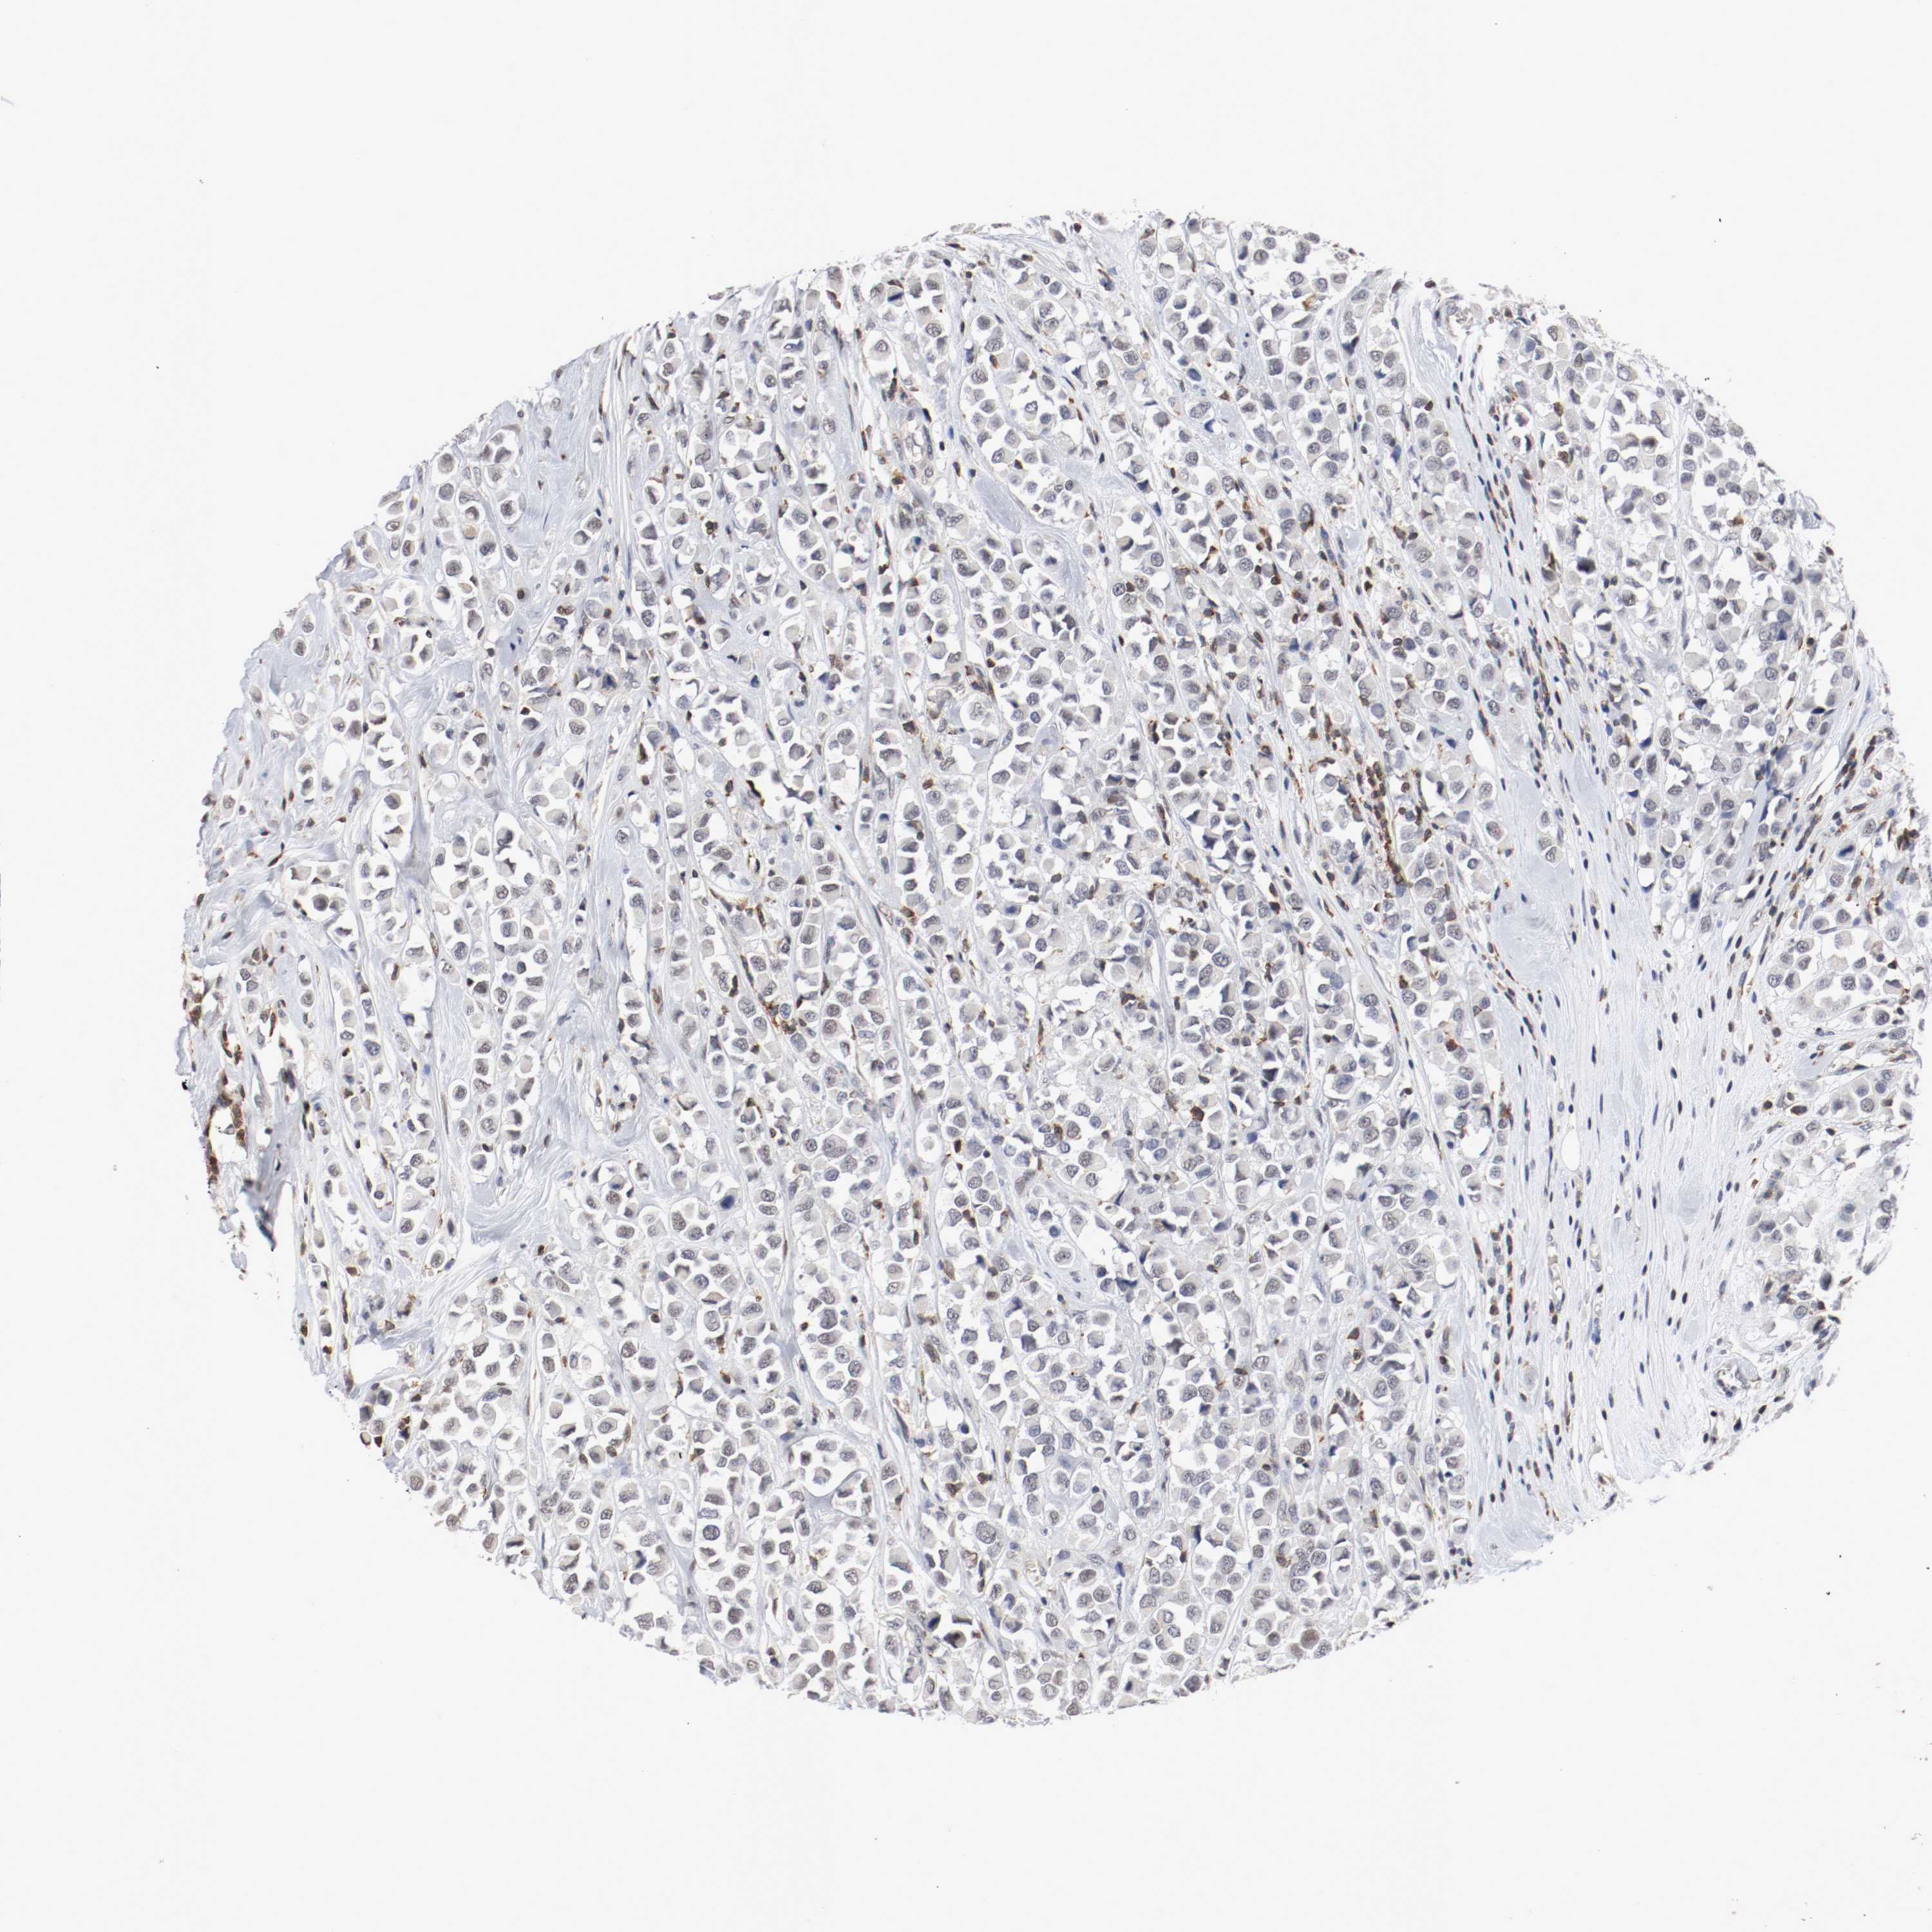

BRCA TCGA BRCA VALIDATION PROTEIN EXPRESSION